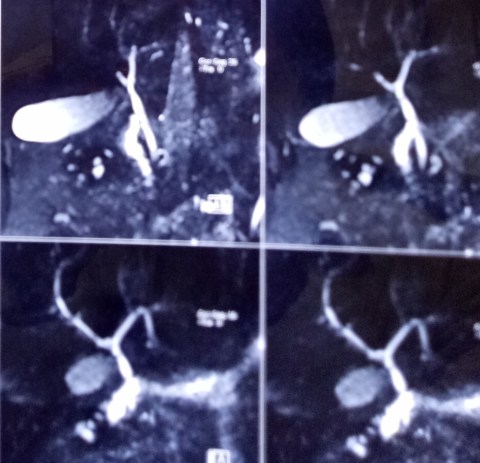

An obese 40 years old lady, having consulted Columbia Hospital, reported for laparoscopic cholecystectomy. She had elevated serum alkaline phosphatase levels assessed repeatedly over a period of nearly two months, raising a suspicion of CBD stones. However, an MRCP showed no stones and a regular laparoscopic cholecystectomy was done.